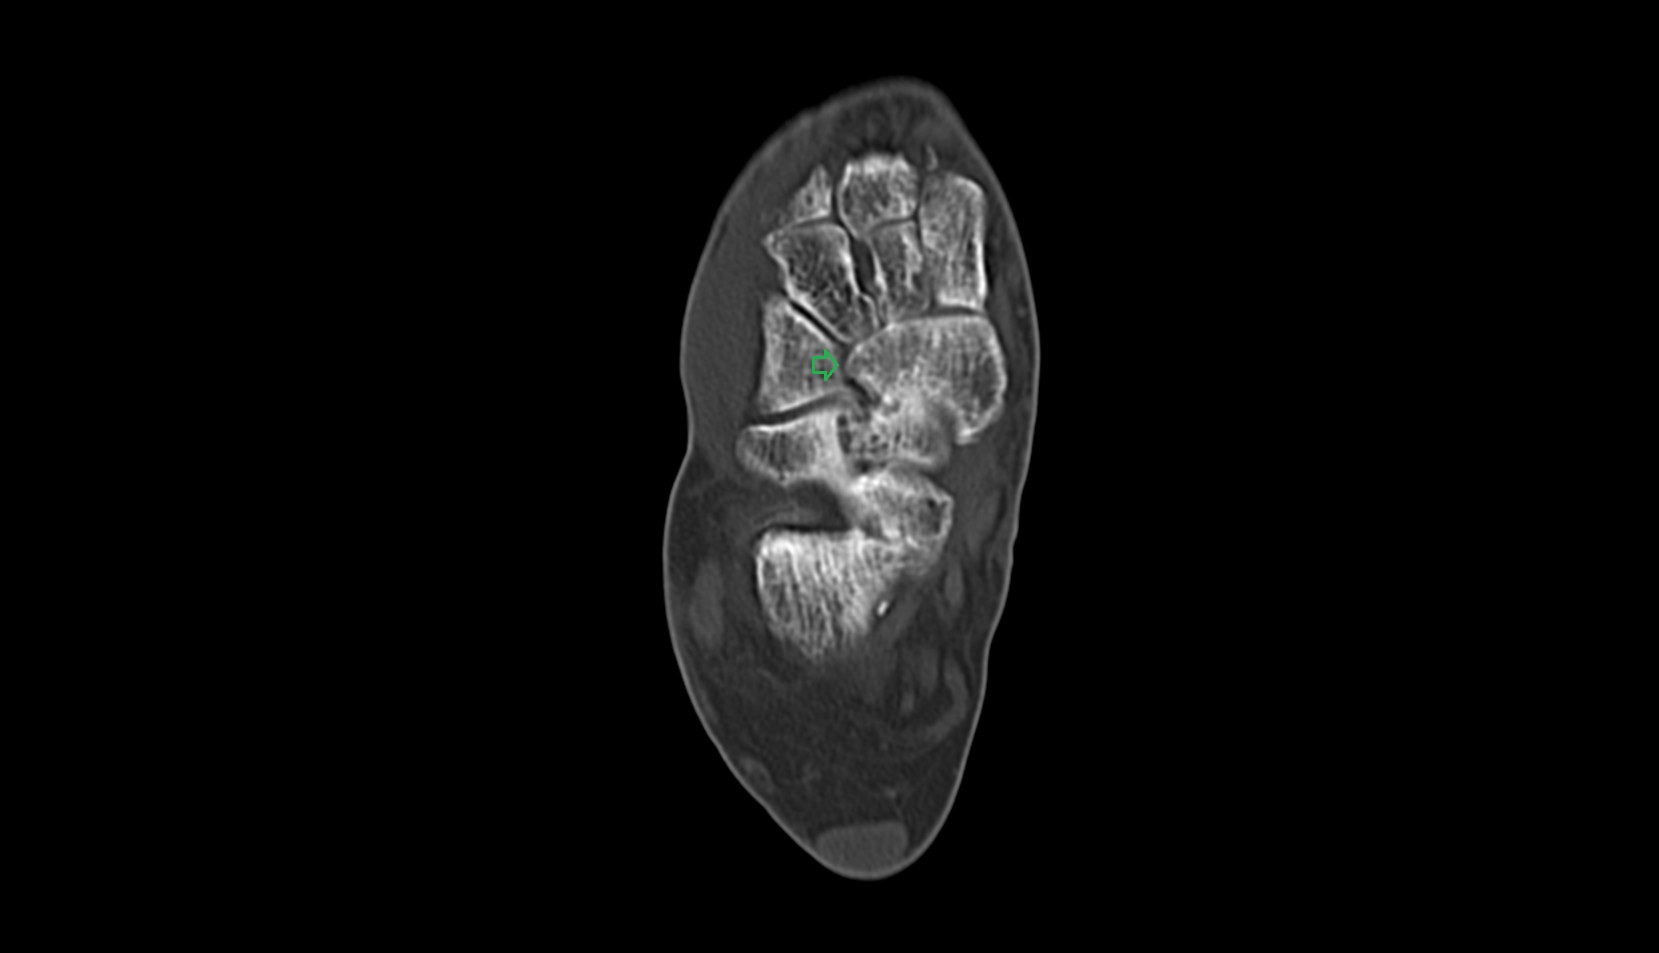

- Talus

- Body of talus

- Calcaneus

- Sustentaculum tali

- Talocalcaneal joint

- Talocalcaneonavicular joint

- Calcaneocuboid joint

- Lateral cuneiform bone

- Medial cuneiform bone

- Intermediate cuneiform bone

- Navicular bone